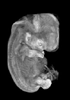

Carnegie Stage 19 (47 post-ovulatory days)

Most embryos at stage 19 are approximately 47-48 post-ovulatory days old and measure 17-20 mm in length. Distinguishing criteria for this stage include straightening of the trunk, the limbs extend nearly directly forward, toe rays are prominent, but interdigital notches have not yet appeared in the foot.

Although some of the photographs below show abnormal embryos, the animations and MRI slice images all depict normal embryos. Abnormal embryos are noted in the titles of the large photos when they are opened.